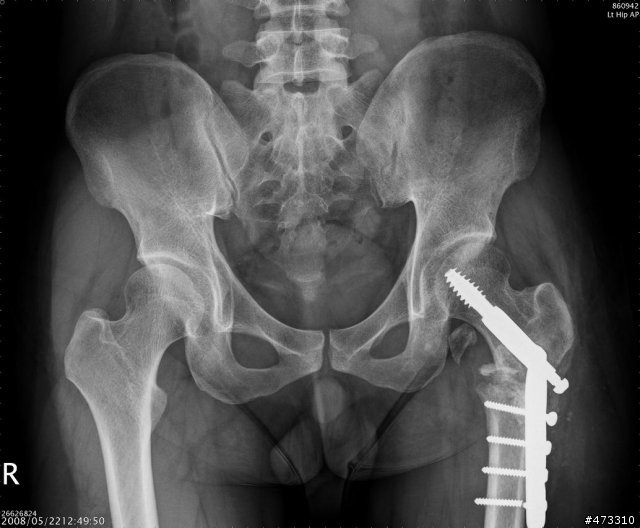

小的我真正重傷害的是在大腿部位

股骨頸與股骨幹本體分離

外加小轉子在復位手術後脫離股股本體跑到坐骨附近

問醫生說阿能處理嗎?他說很難

因為那位置有大量神經叢還有韌帶

大腿總圖

斷裂處特寫

復位手術後兩個月的樣子,有看到一個碎片掉進去坐骨的位置了嗎?